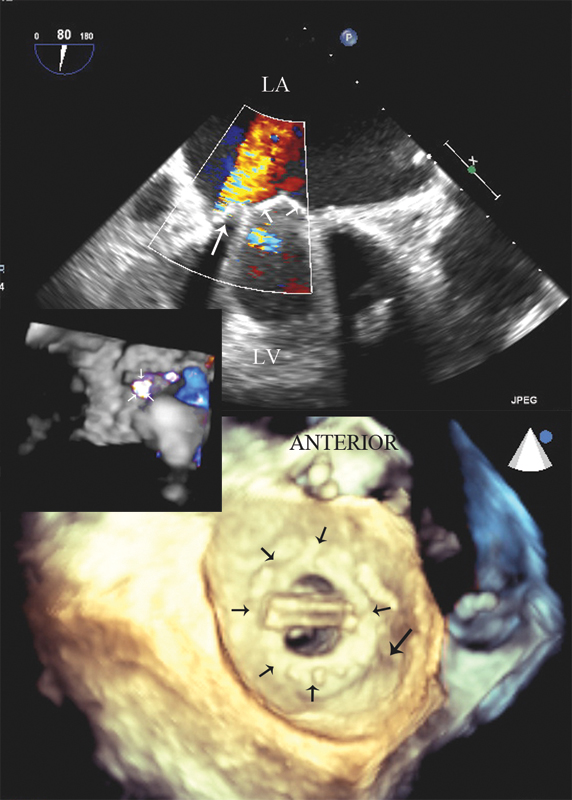

فحوصات تشخيصية لبعض امراض القلب والشرايين التاجية